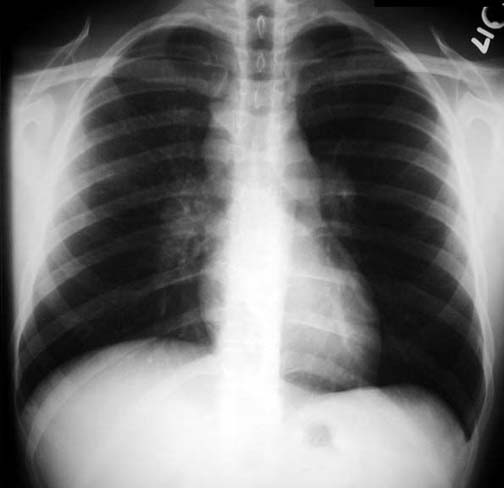

| CXR | CXR CXR CXR | ? Fluid in fissure ? Segmental consolidation | |